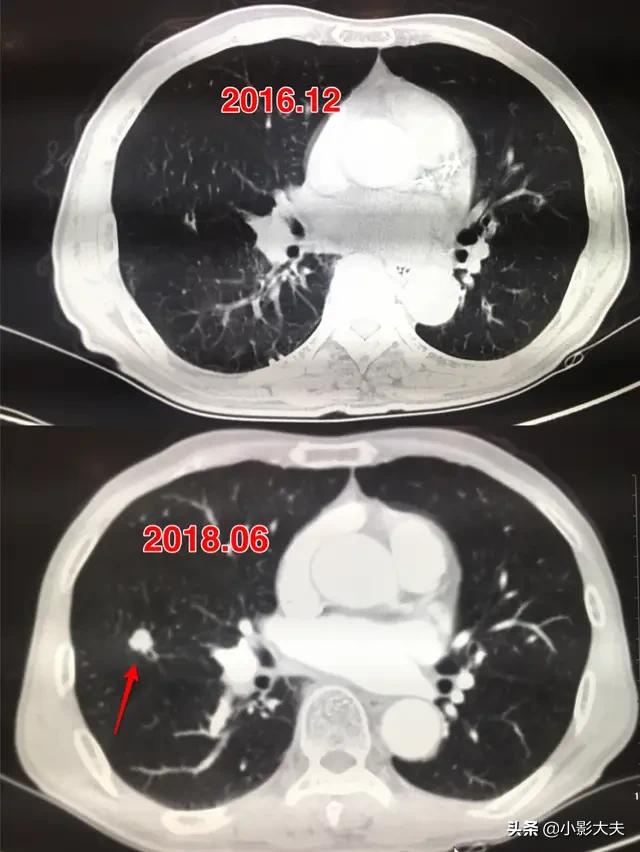

Comme le nodule ci-dessus, il a fallu un an et demi après sa découverte pour qu'il atteigne 1 cm.